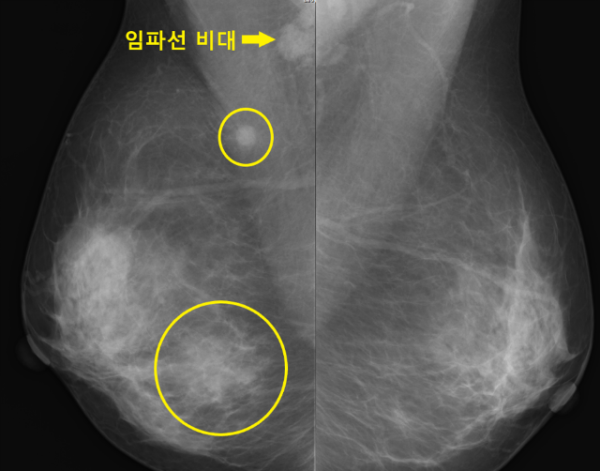

먼저 유방 촬영부터 시행하였습니다.

유방촬영상 오른쪽 유방의 아랫부분에 왼쪽과는 다른 종괴 소견이 관찰되었고 그뿐아니라 윗쪽에도 멍울 소견이 관찰되었고 겨드랑이에도 부어있는 임파선들이 관찰되었습니다.